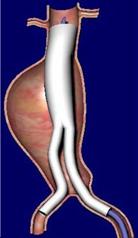

Daha az rahatsızlık verebilecek bir başka tedavi yöntemi ise özel bazı kateterler ile damarın içine girilip, anevrizmanın olduğu damar bölümüne içerden suni damarın yerleştirilmesidir. Endovasküler (damar içinden) anevrizma onarımı olarak bilinen bu yöntem yaklaşık 10 yıllık bir geçmişe sahiptir. Bu yöntemde karından kesi yapılmayıp, sadece kasıklardan yapılan küçük kesiler aracılığı ile röntgen altında işlem gerçekleştirilir.

Anevrizmanın olduğu yere getirilen suni damar şişirilir ev dikiş yerine içerden özel kancalar ile damar tutturulur. Hastalar işlem sonrası hastanede bir iki gün yatıp taburcu edilirler. Bu yöntem anevrizmalı hastaların ancak bir bölümü için uygundur. Anevrizmanın içine suni damar yerleştirildikten sonra anevrizma büyümeye devam edebilir hatta rüptüre olabilir. Bu yüzden hastaların işlem sonrası aralıklı olarak bilgisayarlı tomografi veya renkli Doppler ultrasonografi ile takibi gereklidir. Bu açıdan bu yöntem açık ameliyat yönteminin tersine anevrizmayı her zaman kalıcı olarak tedavi etmez.